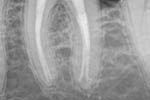

Revisionsbehandlung eines Unterkiefermolaren (37) vor geplanter Überkronung (Dr. Maik Göbbels) Download